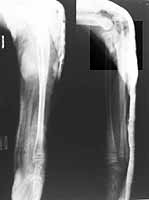

From: T.I. George

I hope that this mail will reach the list. Thank you all for the responses. We did closed reductions and POP above elbow slab for immobilisation. I am trying to attach the pictures for your viewing. My worry was if we try to add k wires for stability at the ends of radius, whether that will add insult to injury with regard to growth since both the epiphysis were involved. I would welcome your comments.